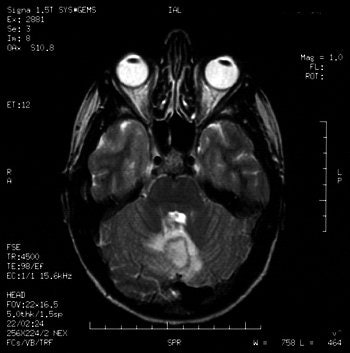

Gadolinium-enhanced MRI scans confirmed the presence of a cerebellar brain abscess in a 22-year-old woman who had undergone tongue piercing four weeks earlier. Images courtesy of Dr Richard Martinello.

Their patient presented with her symptoms four weeks after her tongue piercing. A neurological exam revealed that the patient was alert, and no abnormalities were found in cranial nerve, motor, or sensory function.

However, a brain CT scan revealed a "right cerebellar enhancing lesion with surrounding edema, and an MRI scan with gadolinium confirmed the presence of a solitary brain abscess," the authors reported. The patient underwent a right suboccipital craniotomy to drain the abscess and was then treated with antibiotics. A follow-up CT showed complete resolution of the abscess.